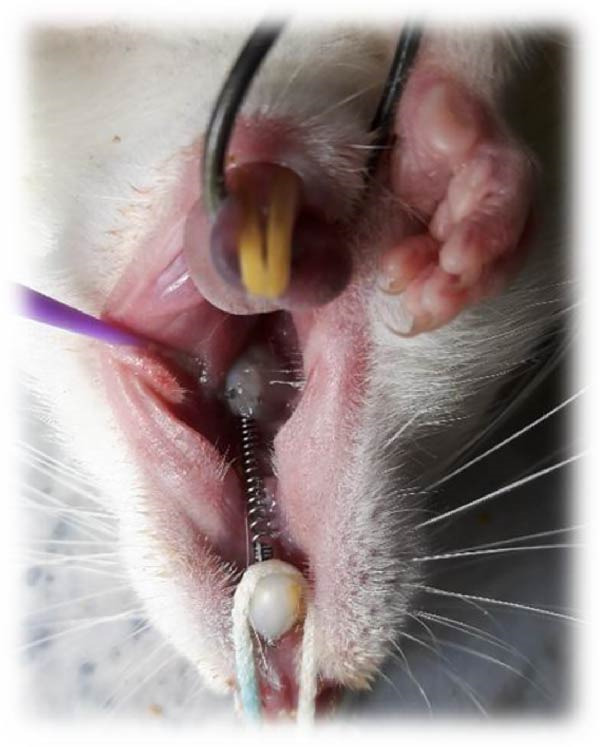

To induce general anesthesia, the rats received 10% ketamine hydrochloride (50 mg/kg; Alfasan, Worden, the Netherlands) and 2% xylazine (2 mg/kg; Alfasan, Worden, the Netherlands) intravenously. After anesthesia induction, the vital signs of the rats were monitored, and they were rolled over every couple of minutes to prevent pulmonary edema. The room temperature was adjusted as well. Nickel–titanium coil springs (6 mm; G & H Franklin) were used to induce OTM. Stainless‐steel wires were connected to the first molars and central incisors of each rat. The teeth were etched with 37% phosphoric acid (Vivadent, USA) for 30 s, rinsed for 10 s, and air‐dried for 15 s. Single Bond (3M ESPE, St. Paul, MN, USA) was applied on the tooth surfaces and cured with an LED curing unit (Woodpecker, Muenster, Germany) with a light intensity of 150 mW/cm2 for 10 s. The orthodontic appliance was secured by the application of Transbond XT light‐cure composite resin (3M ESPE, St. Paul, MN, USA). The coil spring exerted 50 g force [ref. 39] (Figure 2) as measured by a force‐meter. The mandibular central incisors were also shortened to prevent potential damage to the orthodontic appliance. All rats were monitored on a daily basis to ensure correct positioning of the coil spring. In case of its displacement, the rat would be excluded from the study and replaced [ref. 40].